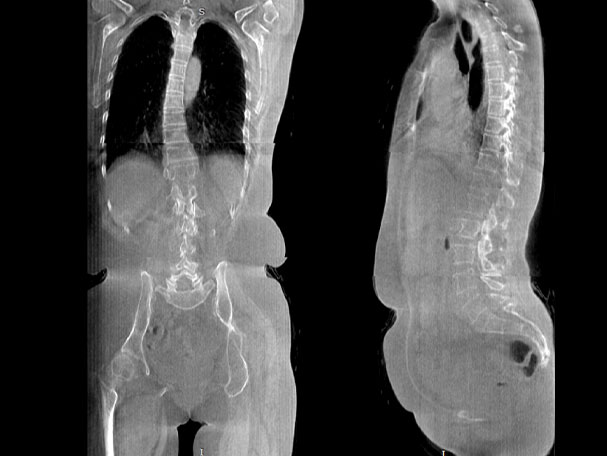

填補常規CT/MR空白

助力術前規劃和術后評估

氣道三維影像重建